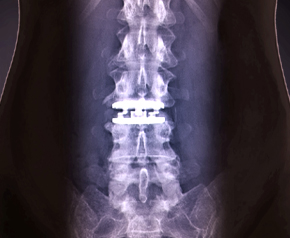

최소침습 척추고정술

특발성 허리굽음

척추측만증 변형수술

인체디스크 교체수술

인공디스크 치환술